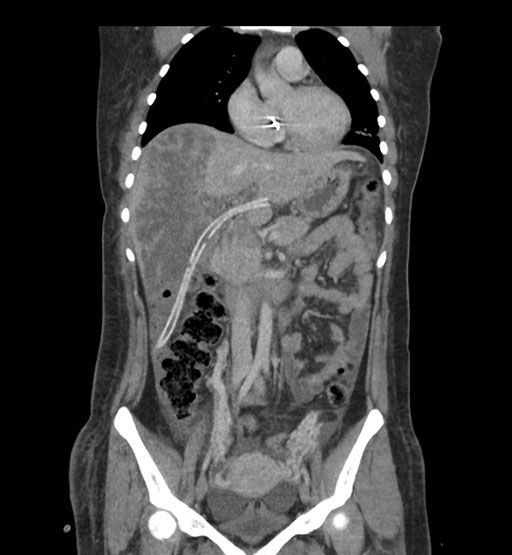

Coronal Arterial

Coronal Venous